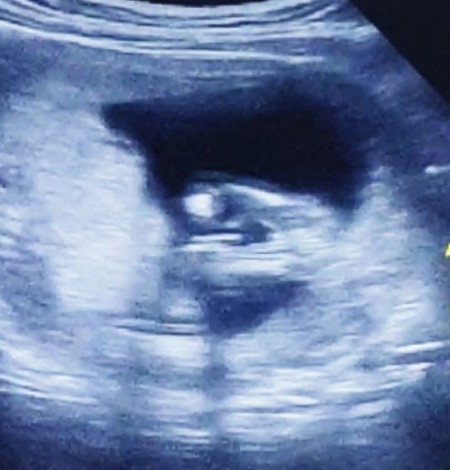

ซาวด์เพศ15วีค

แม่ๆแบบนี้ชายใช่ไหมคะหมอบอกไม่ชัด เลยไม่ได้บอกเพศ#ขอบคุณล่วงหน้านะคะ #ขอบคุณสำหรับคำตอบค่ะ